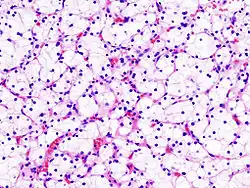

- Grade 1: Inconspicuous and basophilic nucleoli at magnification of 400 times

Clear-cell renal-cell carcinoma. Fuhrman grade = 1. HE, × 400 -